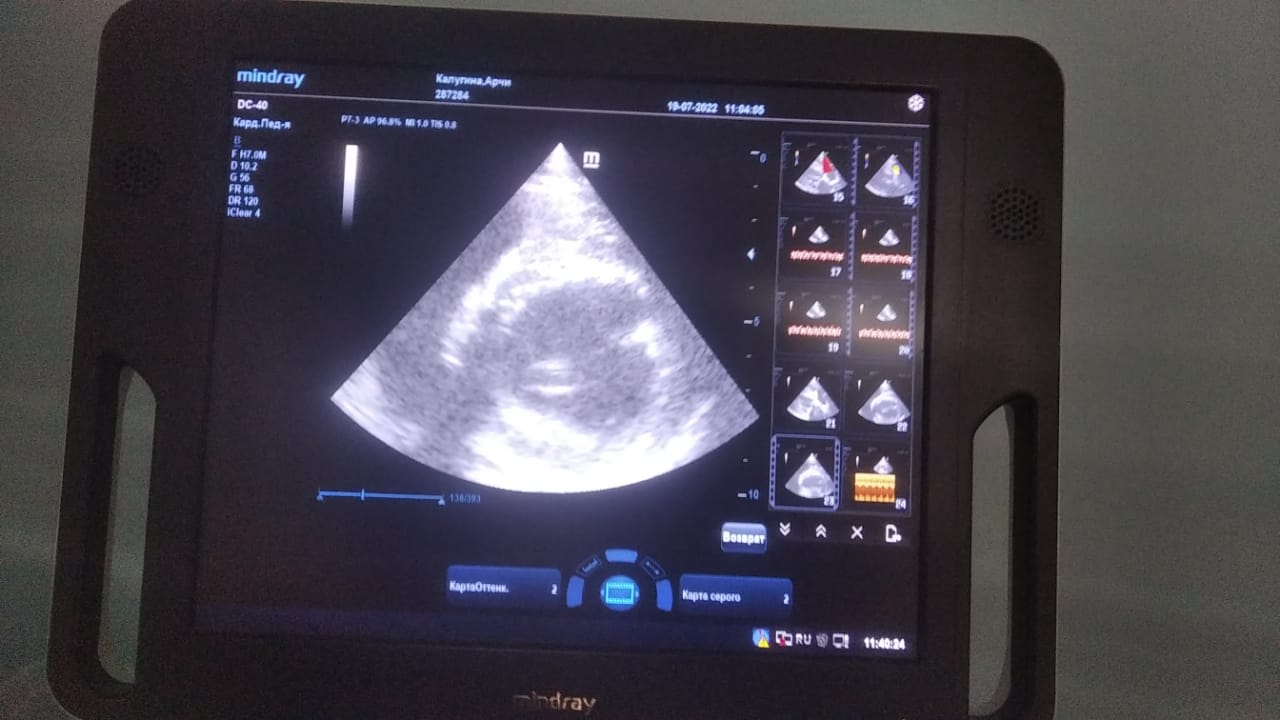

Анализы Арчи. Сердца и легких

Вложения

IMG-20220719-WA0100.jpg

IMG-20220719-WA0102.jpg

IMG-20220719-WA0104.jpg

IMG-20220719-WA0103.jpg

IMG-20220719-WA0105.jpg